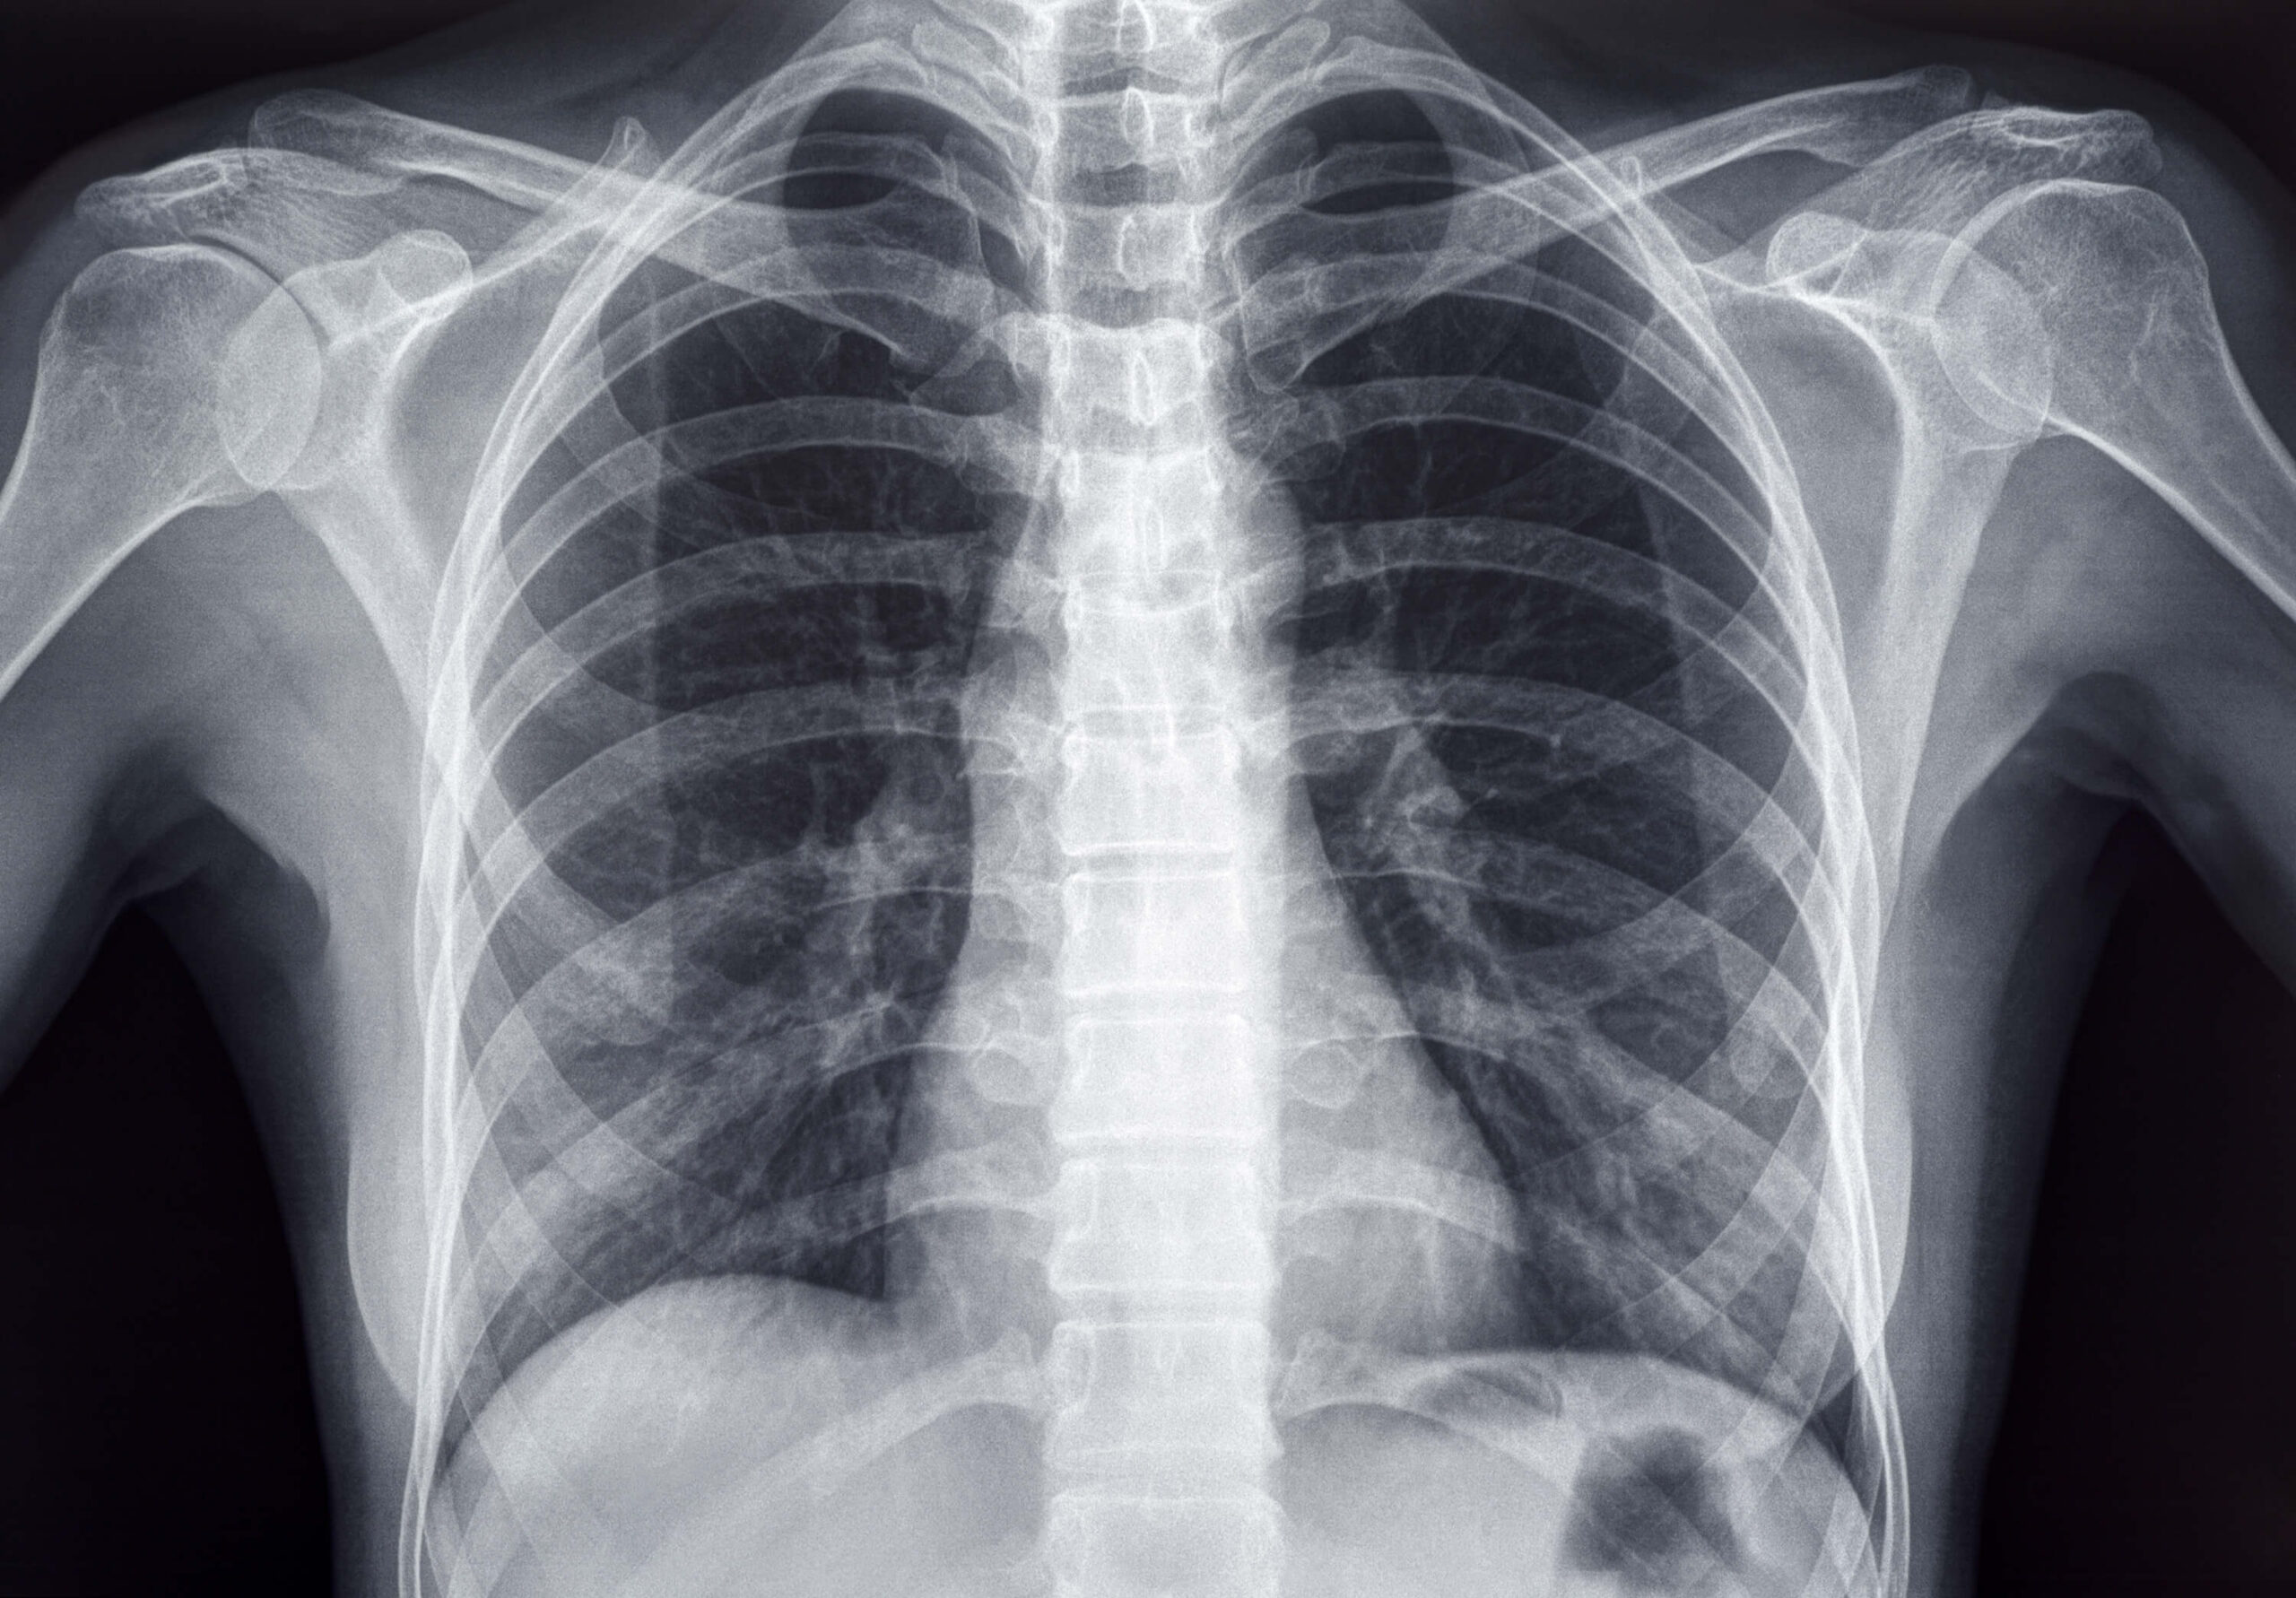

An X-ray is an image of your bones and internal organs. X-rays are most often used to detect bone or joint problems or to check the heart and lungs or abdomen.

X-rays work by sending small amounts of radiation through the body. X-rays are the most frequently used form of medical imaging.